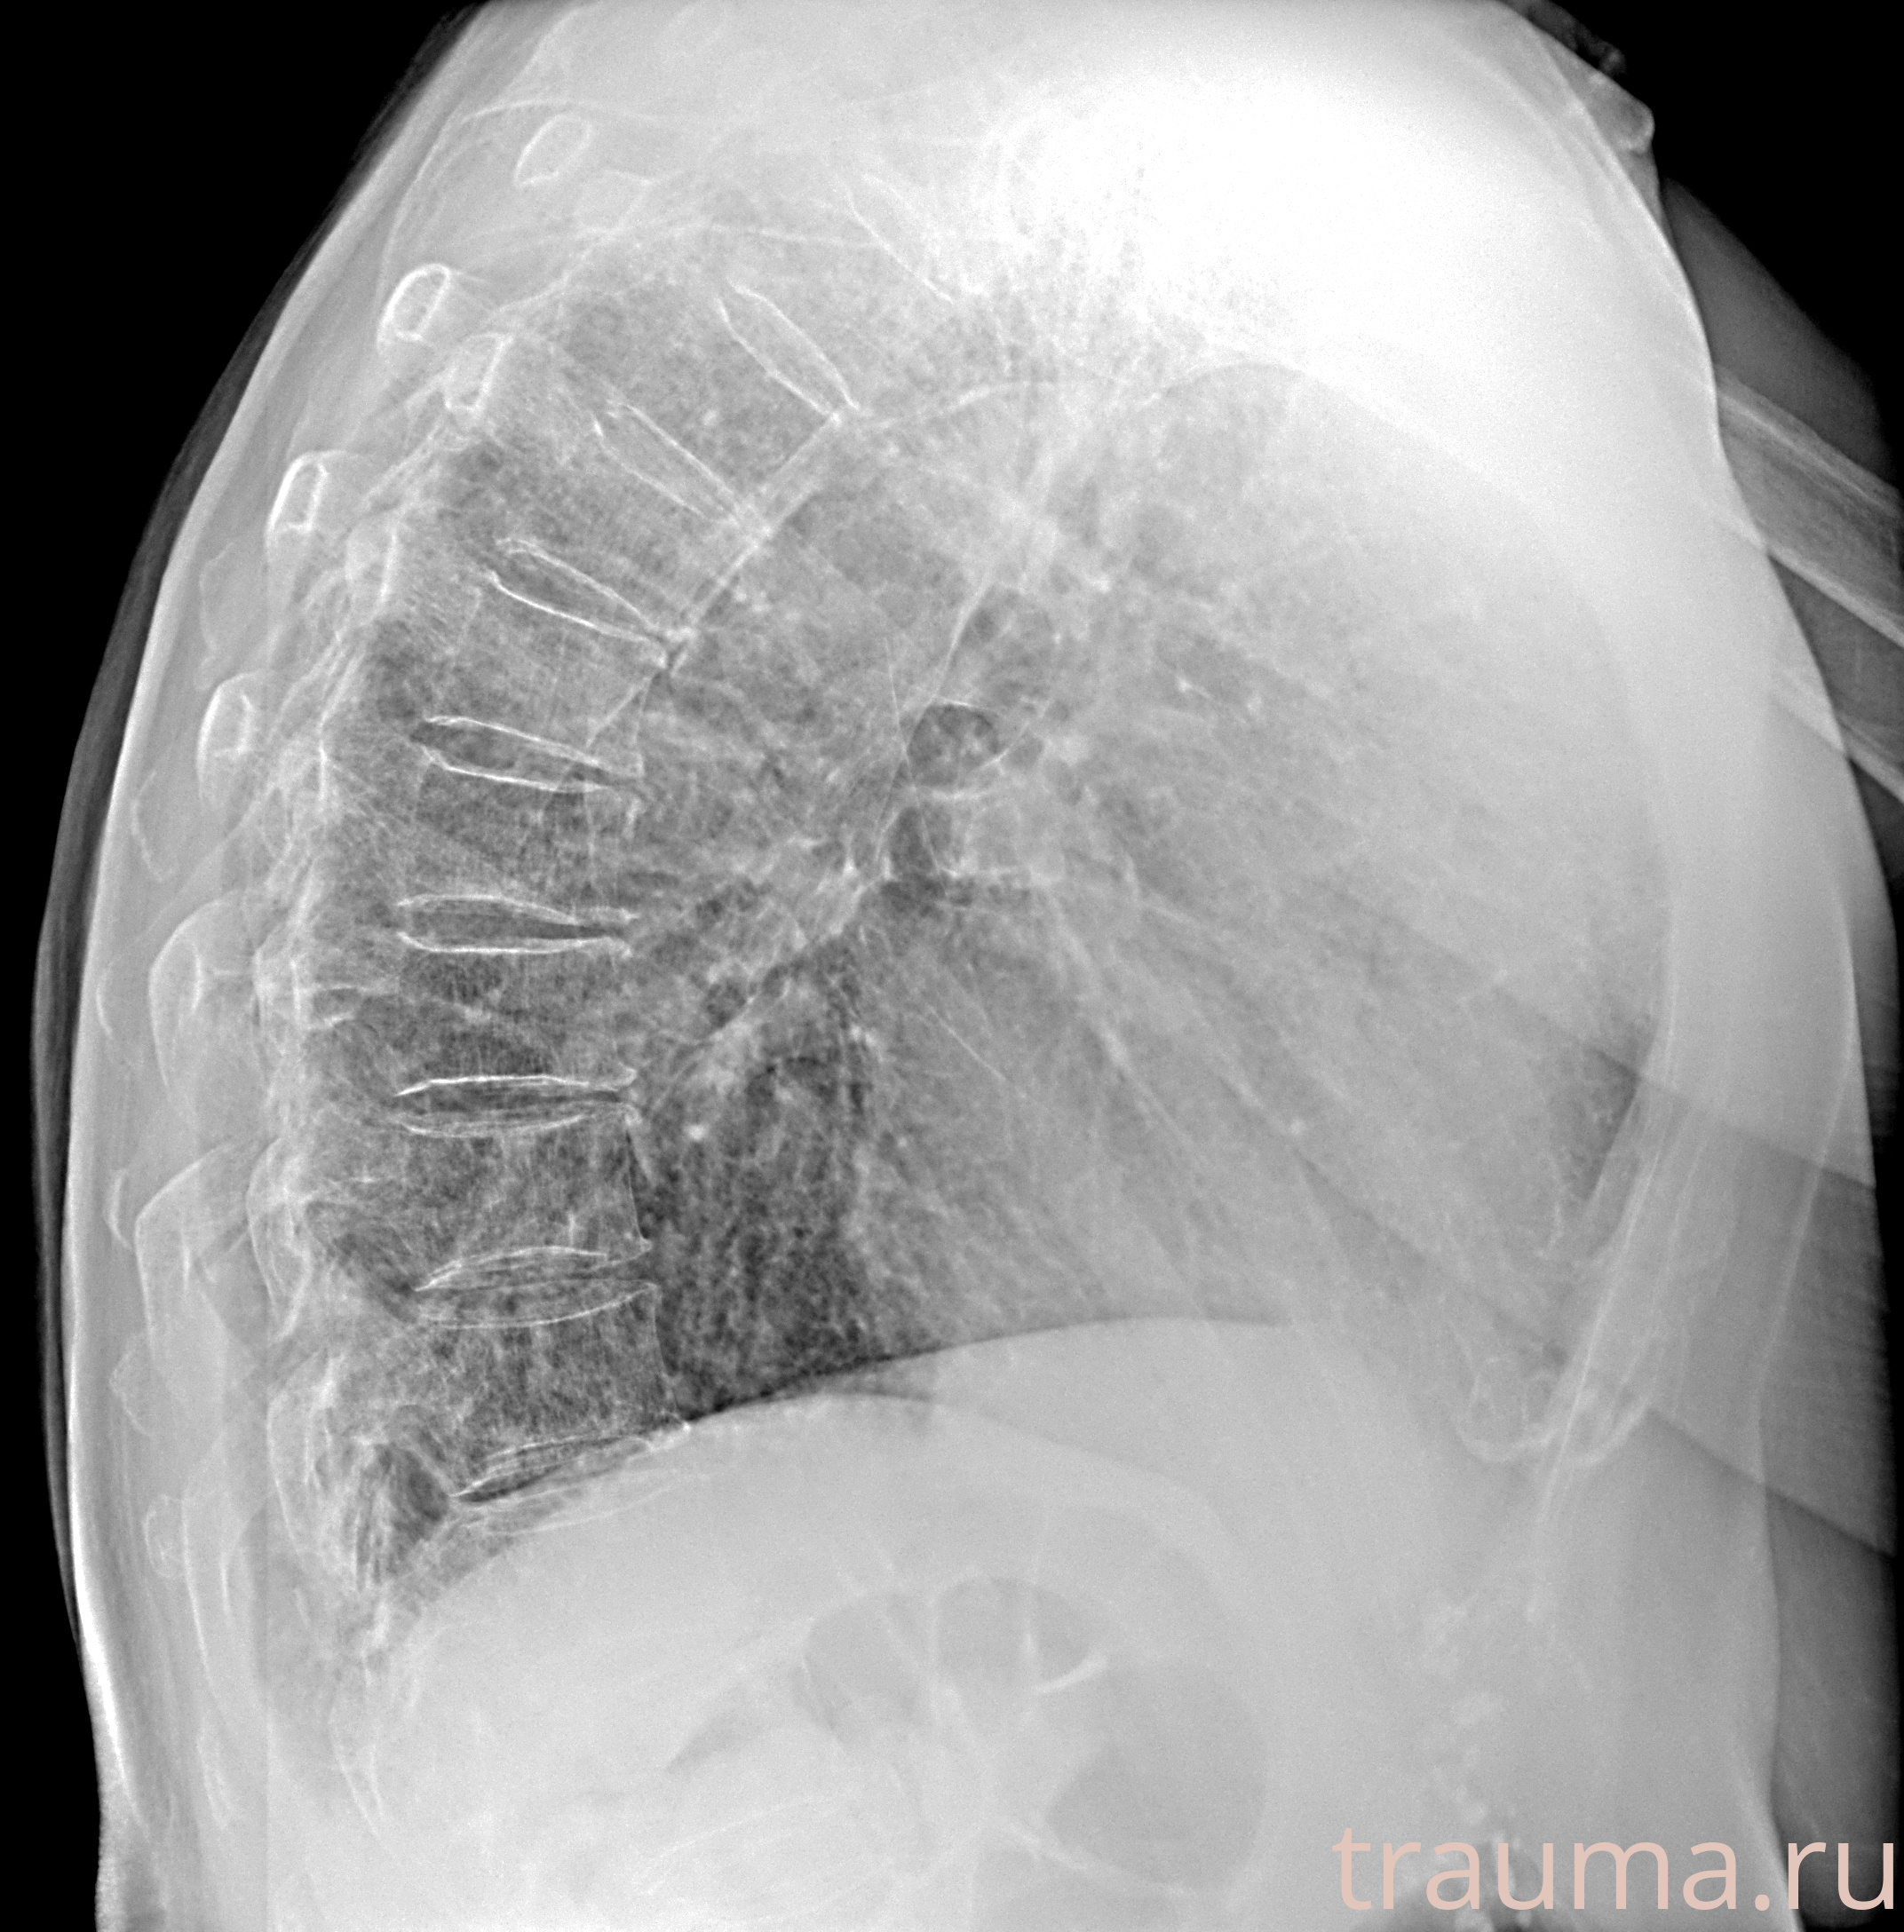

Рентген на дому: по вашему адресу приезжает врач-рентгенолог, травматолог-ортопед с мобильным рентгеновским аппаратом, проводит диагностику травмы или заболевания, делает необходимые рентгенограммы, дает рекомендации по дальнейшему лечению. Получить качественные снимки в домашних условиях возможно благодаря уникальной методике, разработанной МосРентген Центром для института  Склифосовского